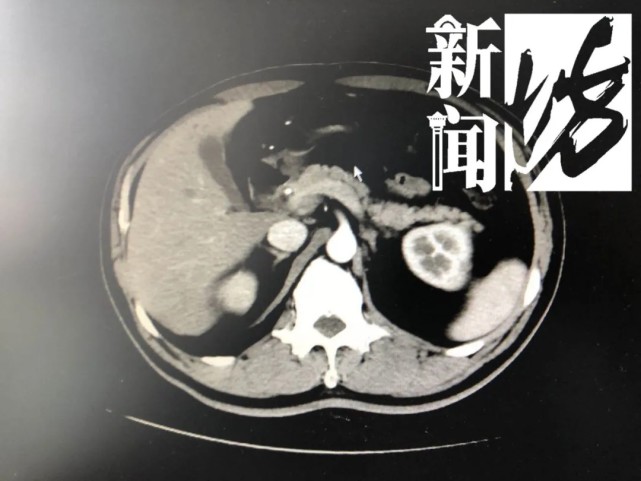

这不查不知道 , 一查情况真的不妙!朱先生体内竟有两个肿瘤!

朱先生的主治医生 杨丰 :病人是比较少见的胃癌合并肠癌 , 称之为同时多原发癌 。

经诊断 , 朱先生被确诊为胃癌和直肠癌 。 原来朱先生之前的暴瘦 , 并不是减肥成功 , 便血也不是痔疮复发 , 一切都是因为肿瘤……医生立即安排朱先生住院手术 , 一次性将两个肿瘤切除 。